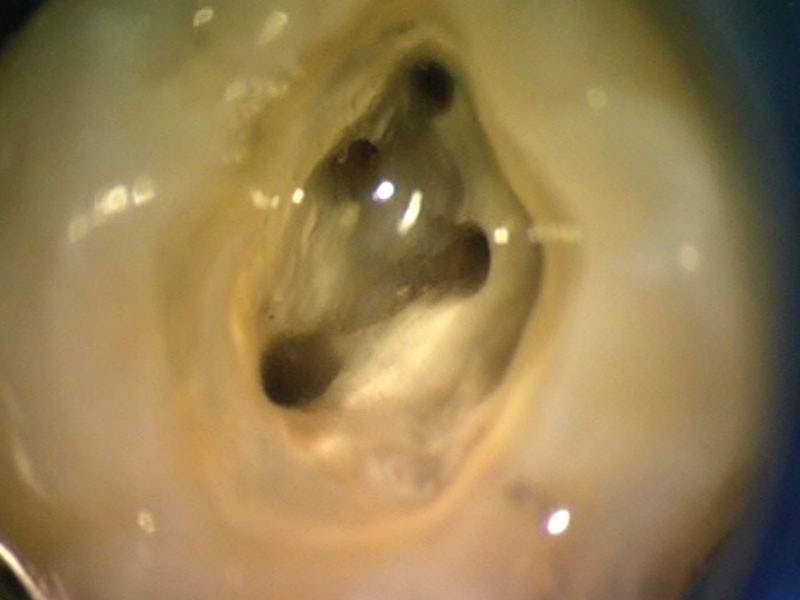

Cavité d’accès et recherche des entrées canalaires.

La cavité d’accès est réalisée selon un contour précis dépendant de la dent, de son anatomie et position sur l’arcade et d’éventuelles réactions dentino-pulpaires (2). L’approfondissement…